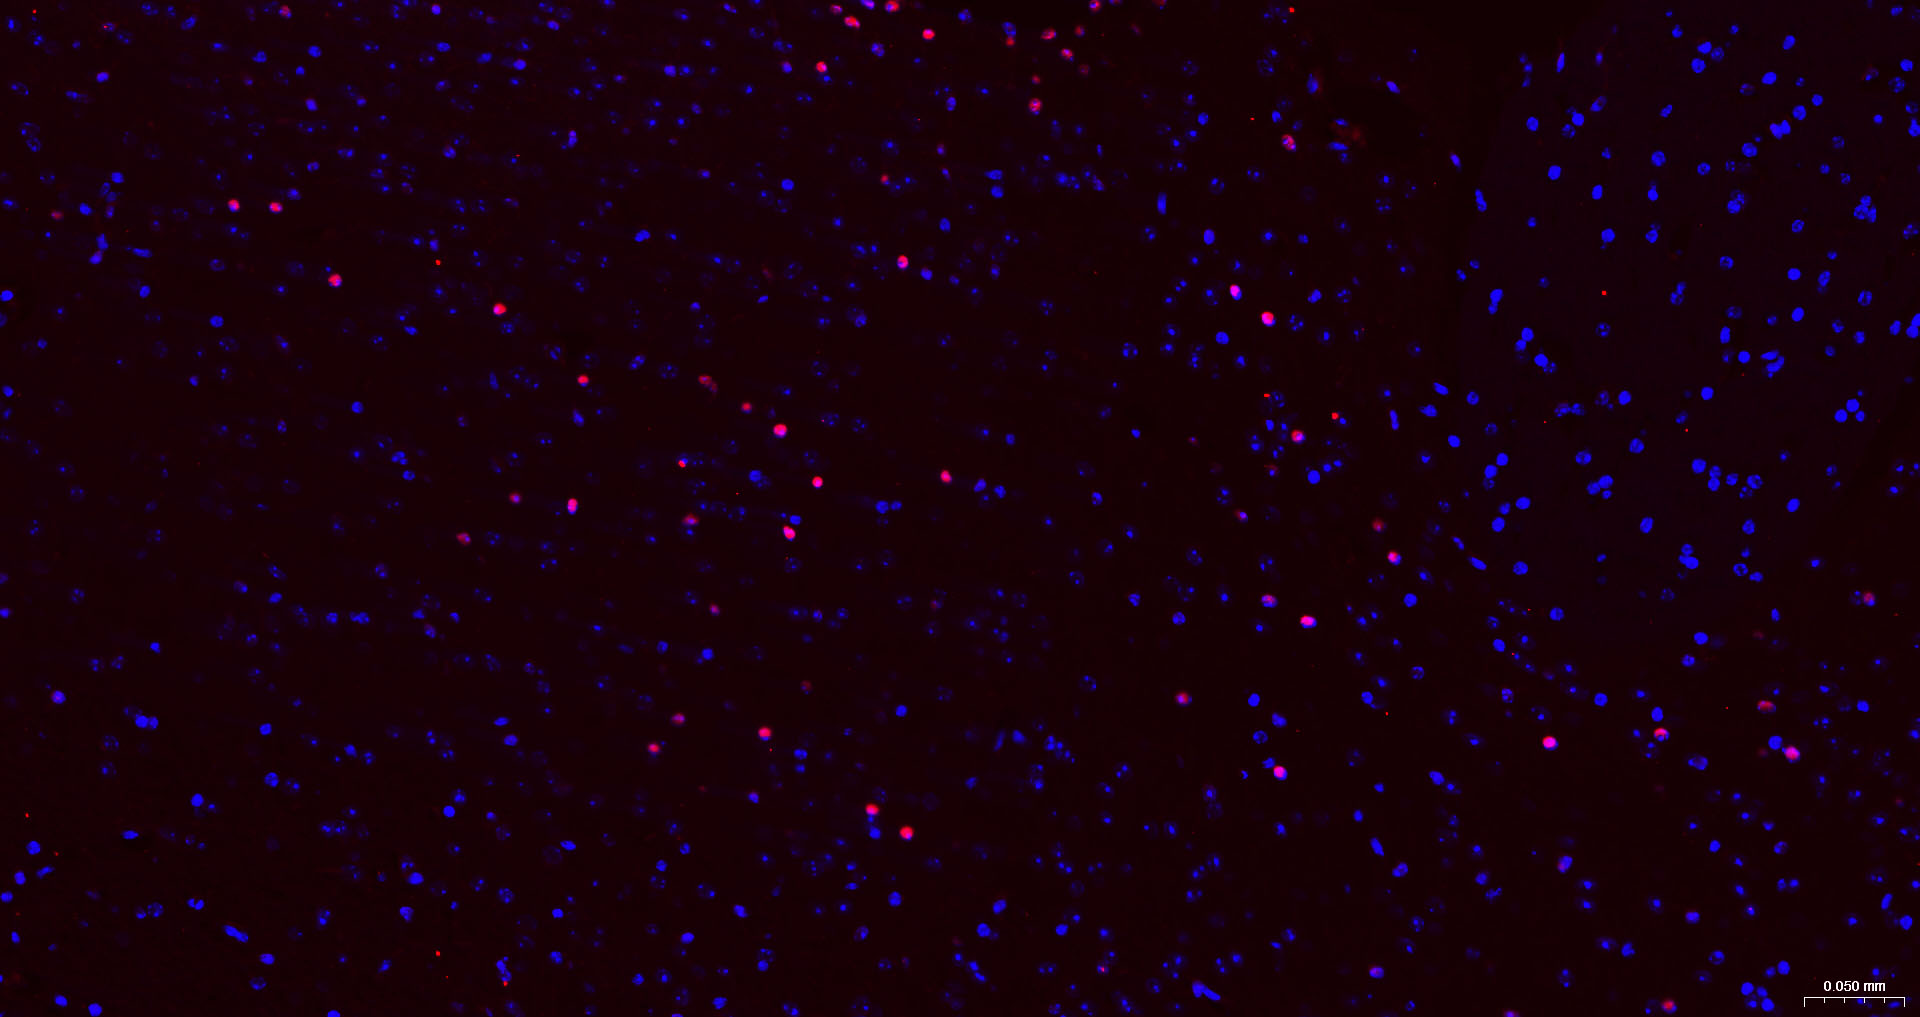

• IF(IHC-P)

IF(IHC-P) IFIHC-P1:200-1000